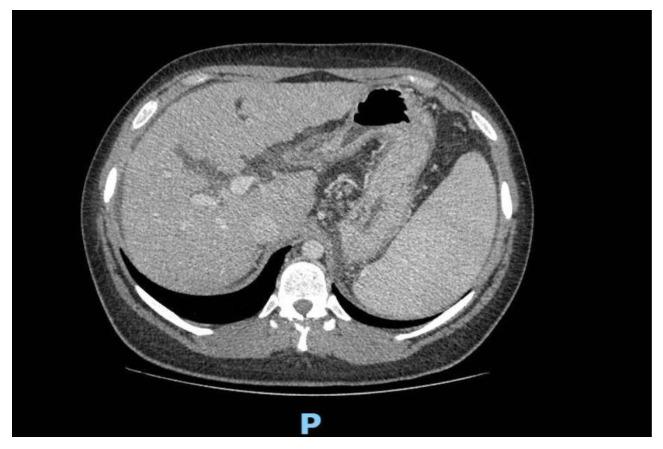

Wilson's disease (WD) is a biallelic disease-causing variant in the gene on chromosome 13q14.3 that results in copper accumulation in many organs, particularly the liver and brain. The phenotypic spectrum is wide and symptoms at onset can be heterogeneous. We describe two Sicilian siblings, a young man and his elder sister, both compound heterozygous for the variants c.1286-2A>G and c.2668G>A (p.Val890Met) in the gene. The male patient presented with liver cirrhosis, which quickly progressed to end-stage liver disease (Child-Pugh score = C10), while his sister had moderate steatotic liver disease (SLD). Our findings highlight that SLD may not always be related to obesity in overweight patients, especially when there are other potential risk factors such as a family history of chronic liver disease, or the persistence of high transaminase despite the adoption of adequate dietary and pharmacological intervention. Screening for conditions such as WD could identify patients at risk of developing SLD and avoid delays in diagnosis. Phenotypic variability in WD is considerable; therefore, further studies are needed to identify which WD patients have a greater risk of developing SLD and determine factors that can predict the severity of the disease.

威尔逊病(WD)是一种由位于13号染色体q14.3区域的基因双等位致病变异引起的疾病,该变异导致铜在许多器官中蓄积,尤其是肝脏和大脑。其表型谱广泛,起病时症状可能多种多样。我们描述了两名西西里岛的兄弟姐妹,一名年轻男子及其姐姐,他们在该基因中均为c.1286 - 2A>G和c.2668G>A(p.Val890Met)变异的复合杂合子。男性患者表现为肝硬化,并迅速进展为终末期肝病(Child - Pugh评分 = C10),而他的姐姐患有中度脂肪性肝病(SLD)。我们的研究结果强调,SLD在超重患者中可能并不总是与肥胖相关,特别是当存在其他潜在风险因素时,如慢性肝病家族史,或尽管采取了适当的饮食和药物干预但转氨酶仍持续升高。对WD等疾病进行筛查可以识别出有发展为SLD风险的患者,并避免诊断延误。WD的表型变异性很大;因此,需要进一步研究以确定哪些WD患者发展为SLD的风险更高,并确定可预测疾病严重程度的因素。